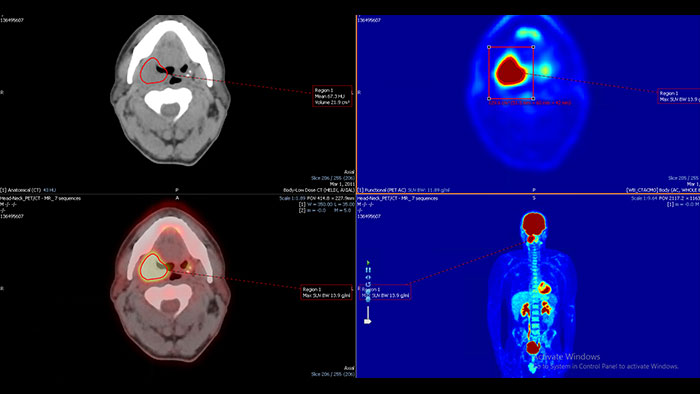

- Mirada Viewer

Mirada NM Viewer: Mirada XD 3.6*

Enhanced user experience for NM reading with a leading NM viewing solution

A comprehensive NM solution, designed to enhance productivity of PET/CT and NM reading. It offers a solution for handling multiple studies requiring rigorous quantification of MV data**.

Benefits

- Quick and configurable protocols for efficient reading.

- Lesion tracking and treatment response.

- Exportable tables and graphs.

- PET\CT and PET\CT\MR registration.

* Mirada is a registered trademark of Mirada inc.

** Please contact local Philips representative for details on multivendor coverage.